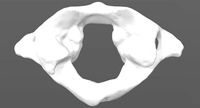

Skull and cervical spine model | 3D

...skull and cervical spine model | 3d

cg trader

this is a 3d print ready model. no non-manifolds. the size of the model is